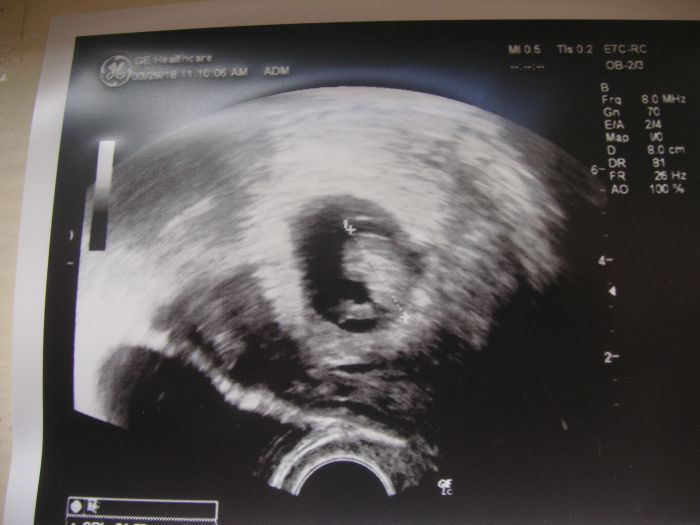

Ahoj holky, pri posledni kontrole mi doktorka rikala, ze je plod velmi maly, priblizne o tyden mensi, nez by mel byt (mela jsem byt 6+4 a plod byl pry cca 5+5). Maly je pry i ten zloudkovy vacek, ktery ho ma vyzivovat. Nicmene srdicko bylo aktivni. Pridala mi Utrogestan na 1-0-2. Kdyz jsem odchazela, jeste dodala, at se zatim pro jistotu z tehotenstvi moc neraduju....Na dalsi kontrolu mam jit po tydnu ted v patek. Jak se kontrola blizi, zacinam byt vic a vic nervoznia uz druhou noc se mi zdalo, ze jsem potratila, no magorim! :-) Zazila jste to nektera, ze bylo mimco takhle na zacatku mensi, nez melo byt? A bylo to v pohode nebo ne?